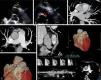

A 54-year-old asymptomatic woman presented to our echocardiography department for assessment of a continuous heart murmur. The transthoracic echocardiogram in parasternal short-axis view (Figure 1A) revealed a tunnel-like communication between the pulmonary artery trunk and the pericardial space (maximum width 8 mm). Color Doppler showed turbulent flow and pulsed wave Doppler showed typical continuous flow (Figure 1B). No valvular abnormalities were noted. There was a normal balance between the right and left ventricle, with preserved global systolic function. The estimated shunt by Qp/Qs was 1.3:1.0. The cardiac computed tomography scan revealed a large coronary artery fistula (CAF) between the left descending coronary artery and pulmonary artery trunk and also an aneurysmatic, tortuous CAF between the right coronary artery and pulmonary artery trunk (Figure 1C–F). A maximal exercise test was performed that excluded myocardial ischemia. She is currently asymptomatic and no cardiac events were noted in two-year follow-up.

(A and B) Transthoracic echocardiogram and color Doppler showing tunnel-like communication (arrows). (C and D) Cross-sectional computed tomography image showing the courses of the fistulae (arrows). (E and F) Three-dimensional volume-rendered multislice multiplanar reconstruction computed tomography views showing the courses of the fistulae (arrows and asterisk).